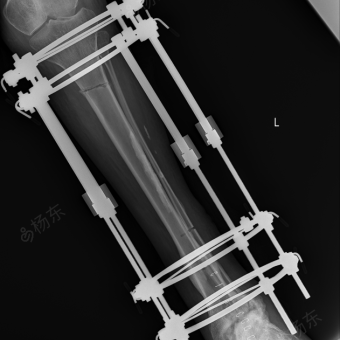

基于ilizarov技术的小腿延长术

车祸右腿缩短再植成功后,利用伊里扎洛夫技术肢体延长12.5cm